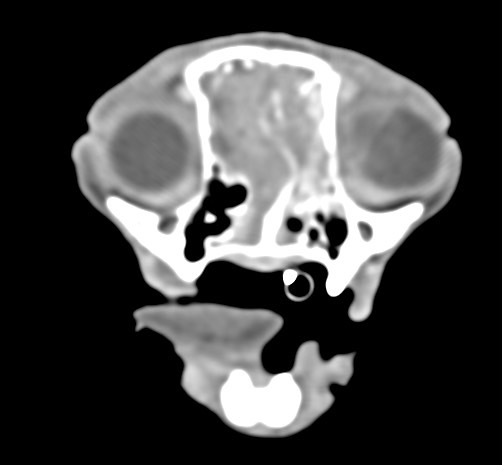

鼻上皮細胞癌

鼻腔症狀是門診中狗貓最常見的主訴之一,但在診斷上卻不那麼容易,在缺乏如電腦斷層、內視鏡、牙科X光等特定設備的情況下,門診醫師多只能嘗試性的給藥觀察,對於慢性、頑固、難治的鼻腔問題往往便束手無策了。

柴犬皮皮因長期有鼻塞、流鼻血、流鼻水的症狀來築心就診,在這之前已經換過兩間醫院,但治療效果都不太好。在一系列的評估後,我們為皮皮安排了電腦斷層以及鼻腔內視鏡的檢查,檢查後發現在皮皮的鼻腔內有疑似腫瘤的團塊,並且向後侵入鼻竇,甚至已經接近大腦。我們運用內視鏡設備採樣取得了團塊的切片,並得到鼻上皮細胞癌的診斷。